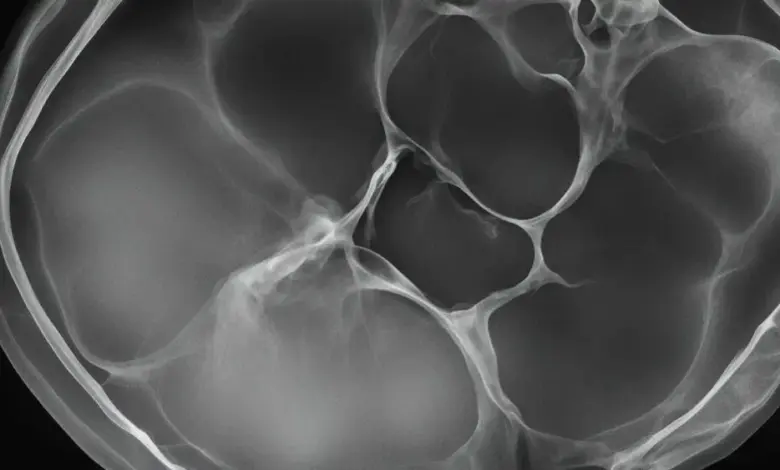

A pedra na vesícula, também conhecida como cálculo biliar, é uma formação sólida que se desenvolve dentro da vesícula biliar.

Ela pode variar em composição, quantidade e tamanho, podendo ter milímetros até centímetros de diâmetro.